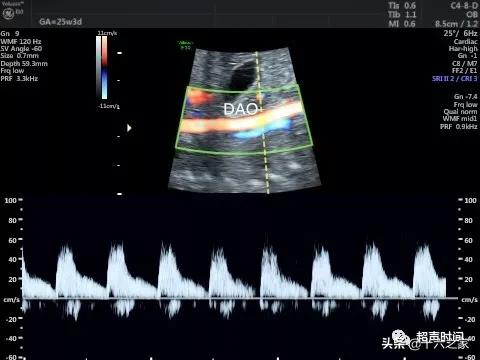

图 1 和视频 1 臀位胎儿腹部横切面示腹主动脉位于脊柱左前方 , 未见下腔静脉 , 扩张的奇静脉位于腹主动脉右后方 , 胃泡位于左侧腹腔 , 脐静脉弓背朝向胃 。 SP :脊柱;DAO :降主动脉;Azygos vein :奇静脉;ST :胃泡;UV :脐静脉

图 3 PW 示胎儿腹主动脉频谱

图 4 PW 示胎儿奇静脉频谱